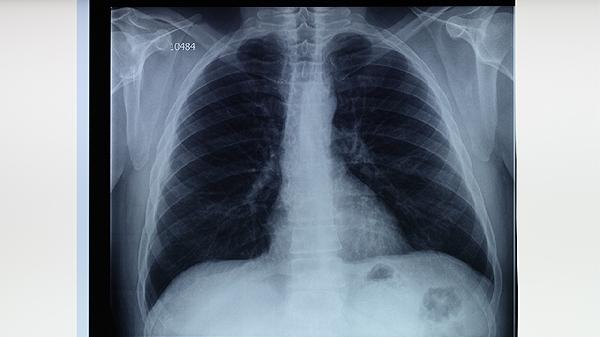

持續(xù)咳嗽咳痰超過2周應進行結核菌素試驗或胸部X線檢查。確診患者需規(guī)范服用異煙肼片、利福平膠囊、吡嗪酰胺片等抗結核藥物6-9個月。密切接觸者應接受預防性治療,可服用異煙肼片3-6個月。治療期間定期復查肝腎功能。